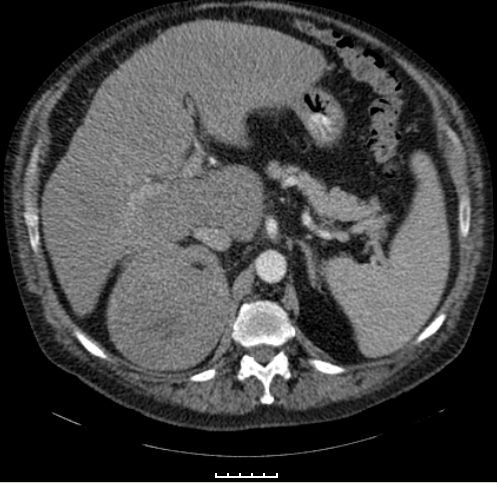

Phaeochromozytom Tumoren des Nebennierenmarks

Nebennieren - Rinden - Tumoren

Staging: ENSAT-Klassifikation

• Umgebungsinfiltration

• Befall regionärer Lymphknoten

• Tumorthrombus in der Vena cava inferior

• Tumorthrombus in derVena renalis

Diagnostik